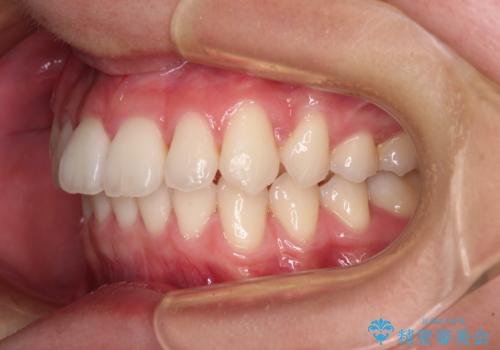

思っていたよりも早くクロスバイトは改善され、歯髄壊死に至ることなく、無事に治療を終えることができました。

クロスバイト改善中には歯髄壊死を起こすリスクがあるため、神経に問題がないか確認しながら治療を進めて行く必要があります。